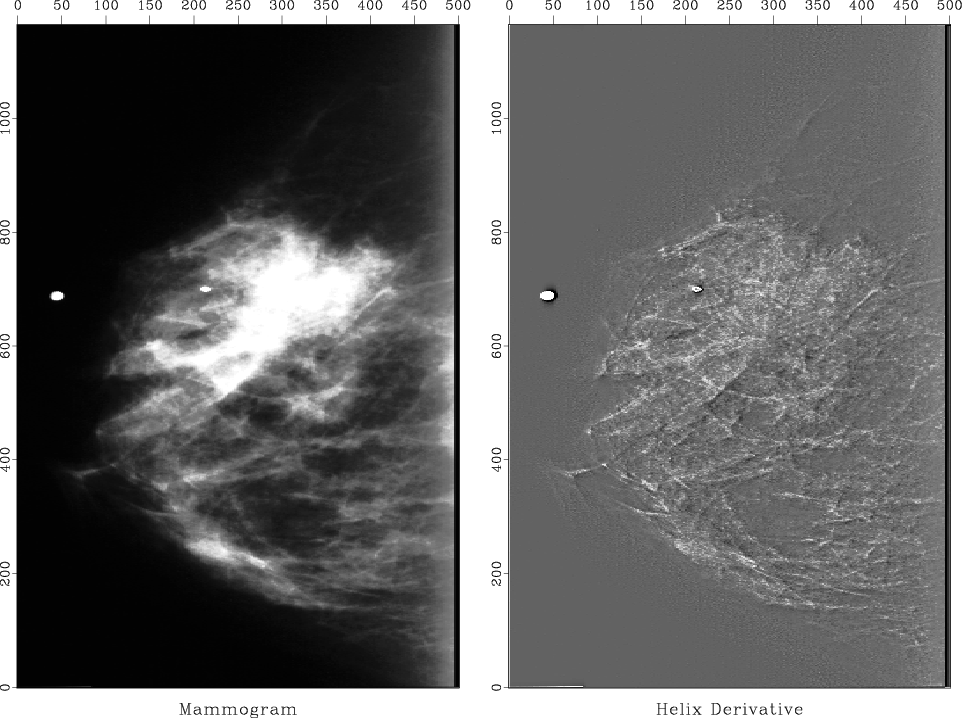

Figure 13.

Mammogram (medical X-ray). The cancer is the ``spoked wheel.'' (I apologize for the inability of paper publishing technology to exhibit a clear grey image.) The tiny white circles are metal foil used for navigation. The little halo around a circle exhibits the impulse response of the helix derivative.

I prepared a half dozen medical X-rays like Figure 13. The doctor brought her young son to my office one evening to evaluate the results. In a dark room, I would show the original X-ray on a big screen and then suddenly switch to the helix derivative. Every time I did this, her son would exclaim ``Wow!'' The doctor was not so easily impressed, however. She was not accustomed to the unfamiliar image. Fundamentally, the helix derivative applied to her data does compress the dynamic range making weaker features more readily discernible. We were sure of this from theory and various geophysical examples. The subjective problem was her unfamiliarity with our display. I found that I could always spot anomalies more quickly on the filtered display, but then I would feel more comfortable when I would discover those same anomalies also present (though less evident) in the original data. Retrospectively, I felt the doctor would likely have been equally impressed had I used a spatial low-cut filter instead of the helix derivative. This simpler filter would have left the details of her image unchanged (above the cutoff frequency), altering only the low frequencies, thereby allowing me to increase the gain.

First, I had a problem preparing Figure 13. It shows the application of the helix derivative to a medical X-ray. The problem was that the original X-ray was all positive values of brightness, so there was a massive amount of spatial low frequency present. Obviously, an $ x$ -derivative or a $ y$ -derivative would eliminate the low frequency, but the helix derivative did not. This unpleasant surprise arises because the filter in equation (13) was truncated after a finite number of terms. Adding up the terms actually displayed in equation (13), the sum comes to .183, whereas, theoretically the sum of all the terms should be zero. From the ratio of .183/1.791, we can say the filter pushes zero-frequency amplitude 90% of the way to zero value. When the image contains very much zero-frequency amplitude, more coefficients are needed. I did use more, but simply removing the mean saved me from needing a costly number of filter coefficients.